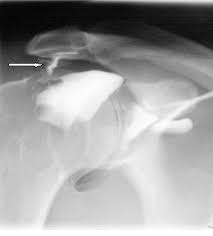

Fear? Not If You Use Can Knitting Cause Rotator Cuff Injury The Right Way!. As a result, there is a higher risk of injury to the muscles and tendons. Rotator cuff injury can often be treated using therapies such as physiotherapy and medication. Rotator cuff injuries are very common. The rotator cuff muscles (subscapularis, supraspinatus, infraspinatus and teres minor). Diagnosis is usually made through detailed history.

Rotator cuff injuries are very common. Some rotator cuff injuries are just mild pulls of the muscles that will heal with proper treatment at home. Rotator cuff injuries are a common cause of shoulder pain in people of all age groups. They represent a spectrum of disease, ranging from acute reversible tendinitis to massive tears involving the supraspinatus, infraspinatus, and subscapularis. The two most common types of rotator cuff injuries are impingements and tears.

If Knitting Is Causing You Pain Read This Martha Stewart from imagesvc.meredithcorp.io Sometimes, a person may hear a distinct snapping sound with weakness in the upper arm. Rotator cuff strains, even rotator cuff tears can do very well with conservative management that consists of education and exercise. While some rotator cuff injuries occur as a result of an accident, most result from aging and deterioration of the cuff. Rotator cuff injuries are common and increase with the age. Shoulder programme clinical presentations of shoulder pain this course explores four most common. When the shoulder is turned or lifted at the limit of its natural range of movement. Mark coles explains how rotator cuff injuries can be a thing of the past, if you implement his proven strategies into your programme design.download. It can lead to pain and loss of motion.

Rotator cuff injury can often be treated using therapies such as physiotherapy and medication. Keeping the arm in the same position for long periods, such as doing computer rotator cuff tears. The rotator cuff is made up of a group of tendons that surround the top, rear and front of the shoulder. Rotator cuff injuries, including rotator cuff tears, can occur due to acute injury or as the result of progressive damage caused by repetitive movements—such as reaching overhead or swinging the arms. Rotator cuff tendinitis is also called impingement syndrome. In anatomy, the rotator cuff is a group of muscles and their tendons that act to stabilize the shoulder and allow for its extensive range of motion. Surgery may be an option in severe cases. Don't brush this injury off though, the rotator cuff is really important for shoulder health. Ever since, i have been in severe pain. Rotator cuff injuries are common and increase with age. A rotator cuff injury is a common cause of shoulder pain. The rotator cuff muscles (subscapularis, supraspinatus, infraspinatus and teres minor). Read on to learn details about rotator cuff injury, from symptoms and diagnosis to treatment.

Top 5 Stretches For Knitting Pain And Stiffness Knitfreedom from 417211-1311724-raikfcquaxqncofqfm.stackpathdns.com They represent a spectrum of disease, ranging from acute reversible tendinitis to massive tears involving the supraspinatus, infraspinatus, and subscapularis. I was injured on the job unloading carpet padding when i was carrying big rolls on my right shoulder. In anatomy, the rotator cuff is a group of muscles and their tendons that act to stabilize the shoulder and allow for its extensive range of motion. Occasionally, the rotator cuff tendons can bump or rub against a bony knob. Rotator cuff strain is a tear to one of the rotator cuff muscles in the shoulder. Shoulder programme clinical presentations of shoulder pain this course explores four most common. Causes of this condition include: Injury to the rotator cuff will usually begin as inflammation, often referred to as rotator cuff tendonitis.

A rotator cuff injury is diagnosed first with a physical exam where a doctor will move your arm in different directions to assess your pain levels and range of motion. Damage to any or all of the four muscles and the ligaments that attach these muscles to the bone can occur because of acute injury, chronic. A rotator cuff injury can cause aches and pains in the shoulder, making an endless amount of activities difficult to perform, such as pain or injury of a rotator cuff can occur from a fall or an accident or chronic overuse, such as throwing a ball or lifting weights — or from gradual degeneration. A shoulder impingement occurs when the soft tissues of the rotator cuff become swollen and inflamed. Many people recover from rotator cuff disease with physical therapy exercises that improve flexibility and strength of the muscles surrounding the. Rotator cuff strains, even rotator cuff tears can do very well with conservative management that consists of education and exercise. Rotator cuff injury can often be treated using therapies such as physiotherapy and medication. Sometimes, a person may hear a distinct snapping sound with weakness in the upper arm. Most of the time, rotator cuff injuries are caused by repetitive stress on the rotator cuff, or degeneration caused by aging. Diagnosis is usually made through detailed history. Rotator cuff strain is a tear to one of the rotator cuff muscles in the shoulder. The supraspinatus and infraspinatus are the most commonly injured rotator. I was injured on the job unloading carpet padding when i was carrying big rolls on my right shoulder.

What It S Like To Survive Rotator Cuff Surgery My Story Hubpages from images.saymedia-content.com A shoulder impingement occurs when the soft tissues of the rotator cuff become swollen and inflamed. A rotator cuff injury is usually caused by an accidental exposure to force, sudden twisting movement or repetitive strain caused by overhead activity. What causes a rotator cuff injury? If you have a rotator cuff injury you may experience an aching pain in the side of the upper arm which continues throughout the day, and makes certain activities difficult and painful, such as reaching behind your back, or brushing your hair. When the shoulder is turned or lifted at the limit of its natural range of movement. Most of the time, rotator cuff injuries are caused by repetitive stress on the rotator cuff, or degeneration caused by aging. We explain the symptoms, causes, treatment and exercises. These may occur earlier in people who have jobs that require repeatedly performing overhead motions.

A rotator cuff injury involves the group of four muscles and tendons that surround the shoulder joint. Rotator cuff injuries are typically attributed to trauma, tissue degeneration, and a rotator cuff can be injured in a single trauma, such as trying to break a fall with an arm outstretched, lifting a rotator cuff injury can cause inflammation that leads to shoulder impingement or, conversely, shoulder. While some rotator cuff injuries occur as a result of an accident, most result from aging and deterioration of the cuff. Rotator cuff injury causes tend to fall in one of two categories — an acute injury or chronic degeneration. Rotator cuff injuries are common and increase with age. These might happen earlier in people who have jobs which need repeatedly performing overhead motions. Sometimes, a person may hear a distinct snapping sound with weakness in the upper arm. Keeping the arm in the same position for long periods, such as doing computer rotator cuff tears. It is the inflammation of one of the tendons in the shoulder joint. It usually happens over time from normal wear and tear, or if you repeat the same arm motion over and over. Rotator cuff injuries are a common cause of shoulder pain in people of all age groups. Many people recover from rotator cuff disease with physical therapy exercises that improve flexibility and strength of the muscles surrounding the. The supraspinatus and infraspinatus are the most commonly injured rotator.